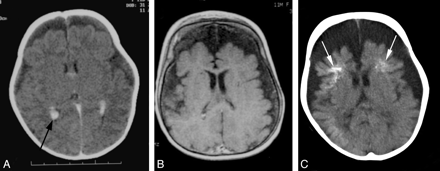

Serial imaging of a child with a clinical complex of bilateral facial PWS, early-onset severe seizures, and fatally progressive encephalopathy. Imaging demonstrates progressive cerebral atrophy and calcification without evidence of pial enhancement. A, Contrast-enhanced CT scan at 1 month of age demonstrates mild cerebral atrophy and bilateral choroid plexus hypertrophy (black arrow). B, Axial T1WI postgadolinium image at 12 months of age shows further cerebral volume loss but no evidence of abnormal pial enhancement. C, CT scan at 15 months of age demonstrates progressive symmetric cerebral volume loss with calcification of the cortex and subcortical white matter, most marked within the frontal lobes bilaterally (white arrows).